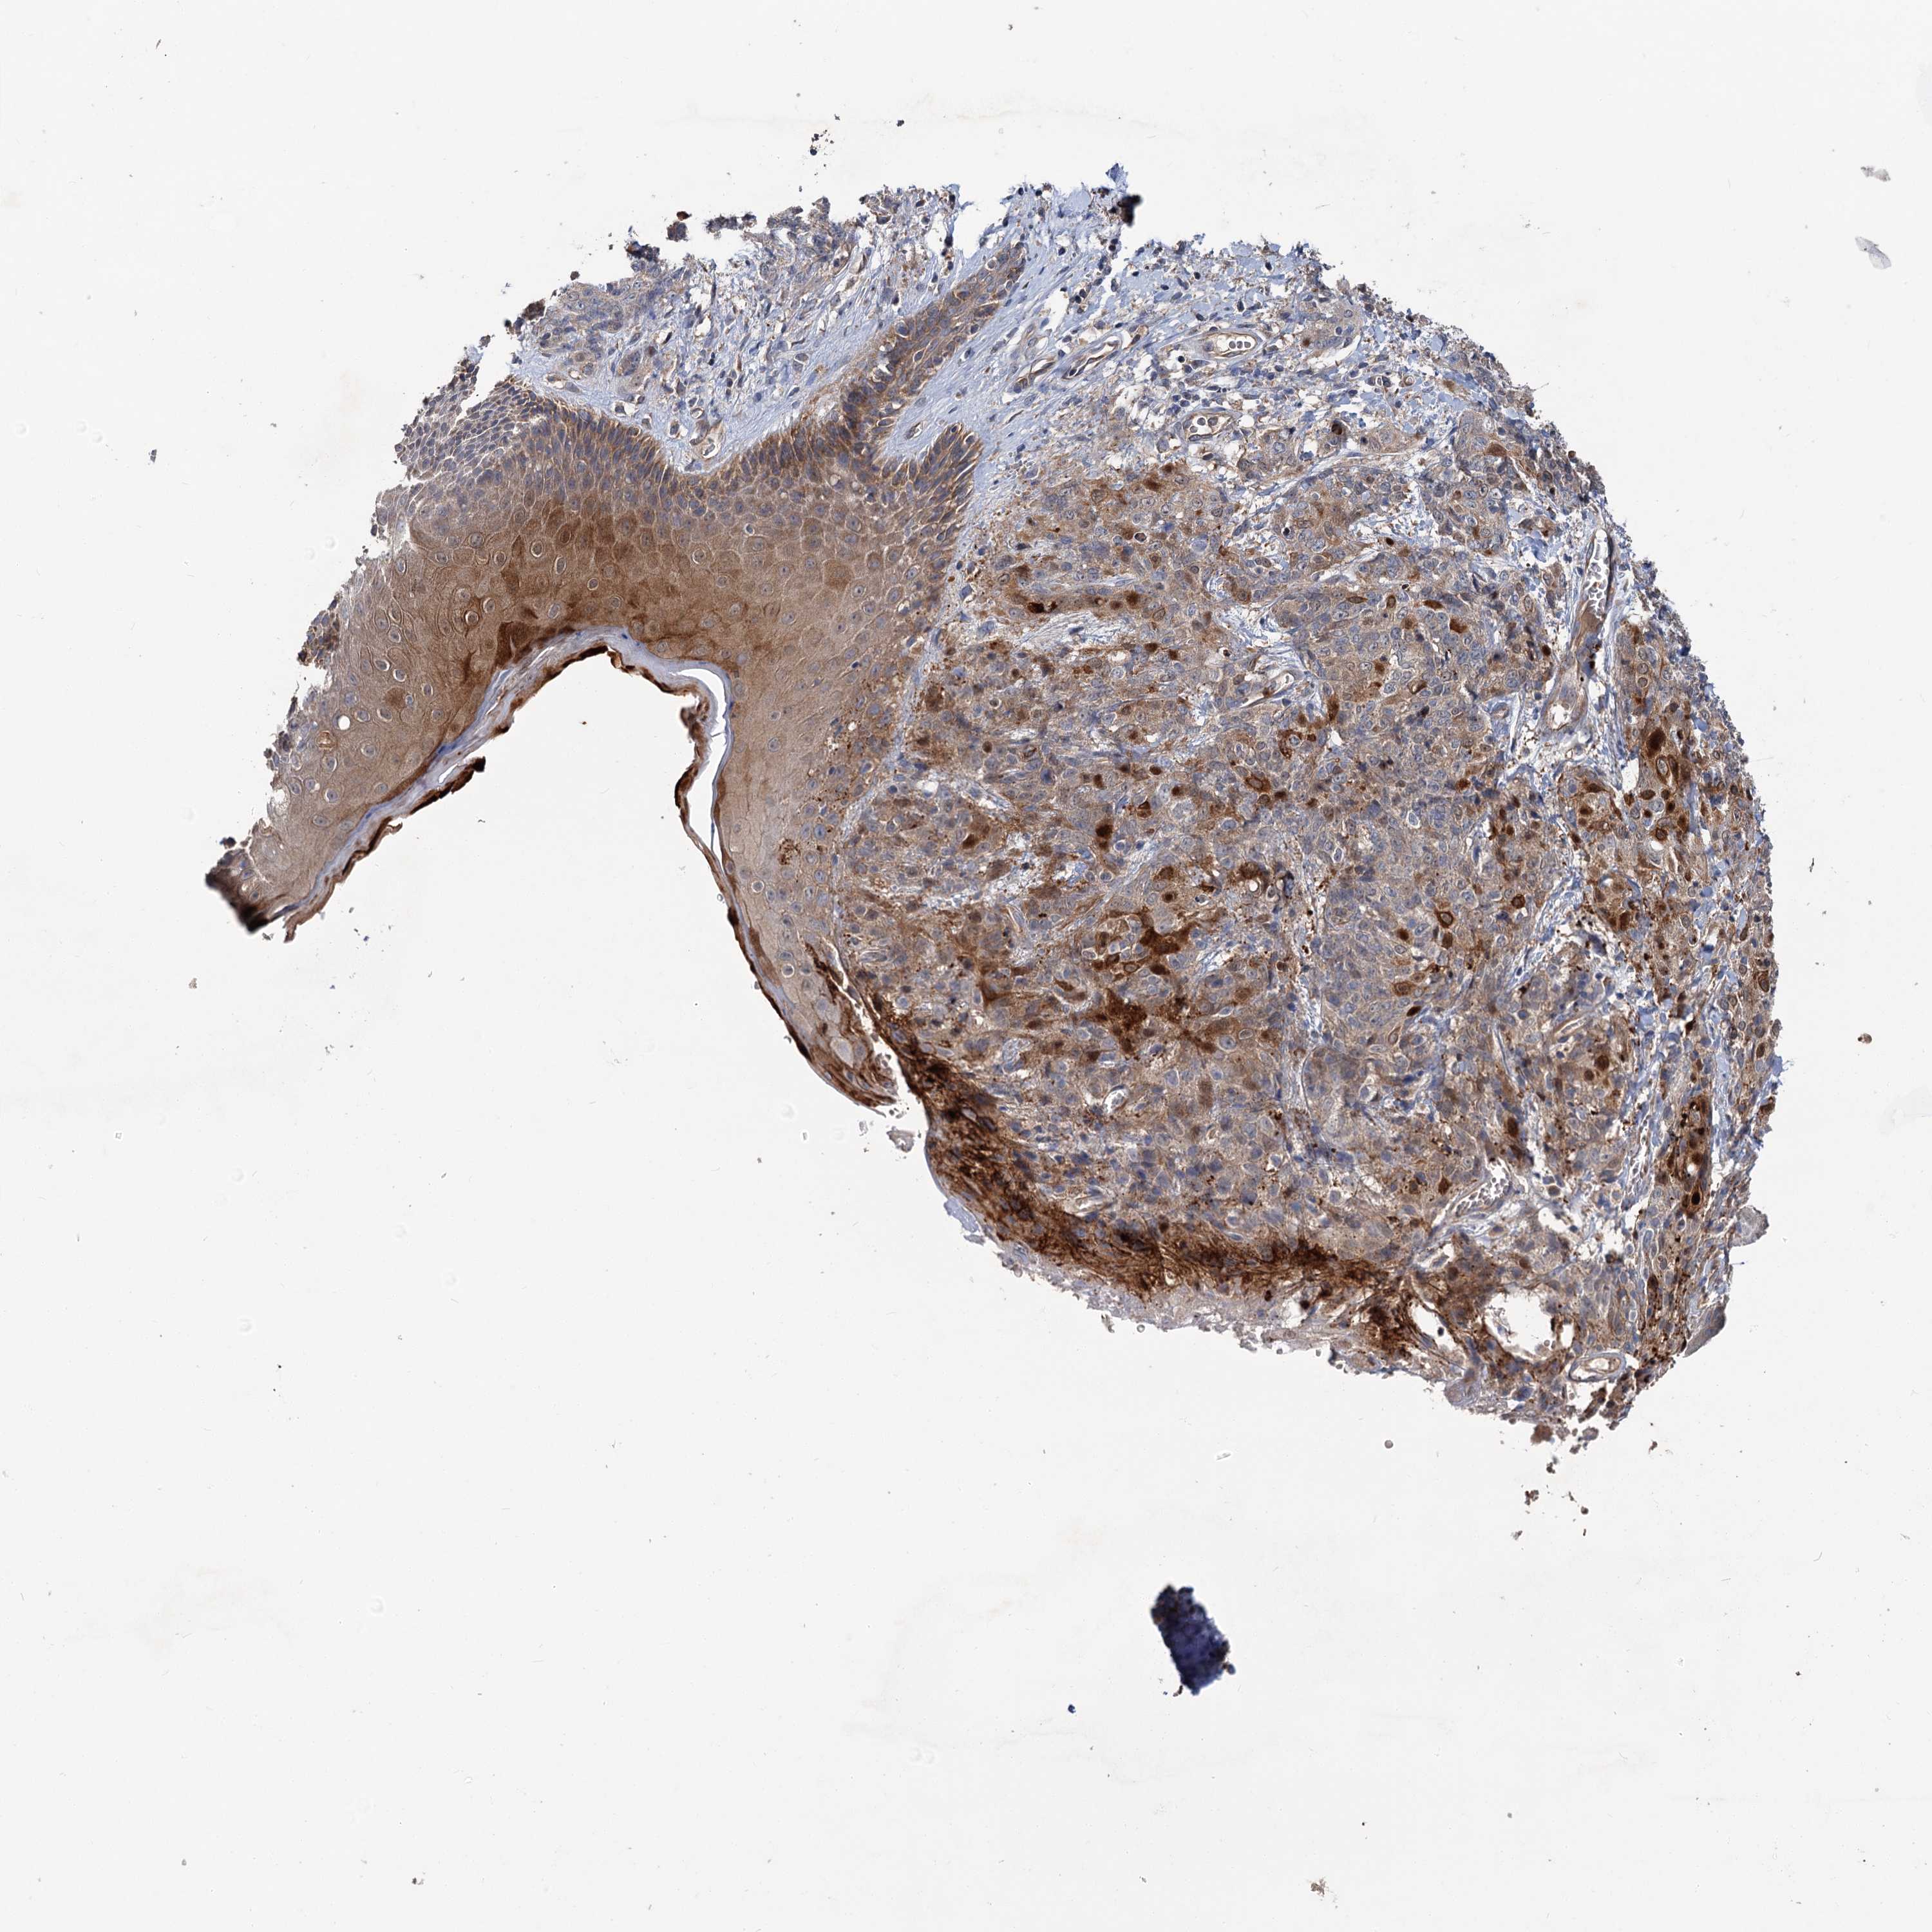

SKIN CANCER - Protein expressioni

A mouse-over function shows sample information and annotation data. Click on an image to view it in a full screen mode. Samples can be filtered based on level of antibody staining by selecting one or several of the following categories: high, medium, low and not detected. The assay and annotation is described here.

Each image is clickable and will lead to virtual microscopy that enables deeper exploration of all samples and also displays staining intensity scores, fraction scores and subcellular localization as well as patient and tissue information for each sample.

Antibody HPA039015

Antibody HPA039016

Squamous cell carcinoma, NOS

Squamous cell carcinoma, metastatic, NOS